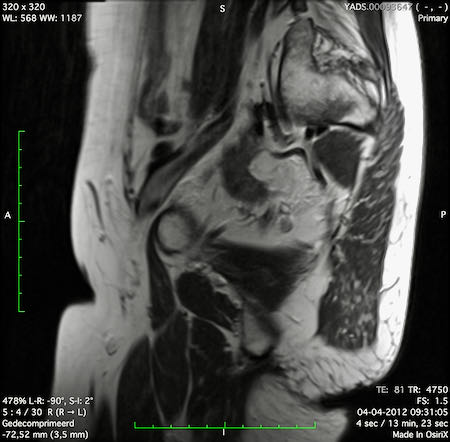

Hình ảnh

Các hình ảnh được cung cấp cho thấy ung thư biểu mô tế bào nhẫn với tình trạng dày lan tỏa thành trực tràng, hình ảnh bia bắn điển hình, và sự xâm lấn mỡ mạc treo trực tràng.